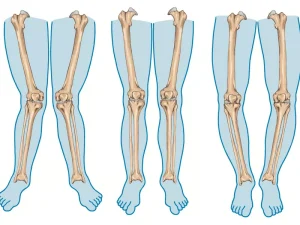

جراحی صافی کف پا یکی از روشهای درمانی است که